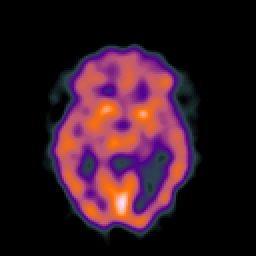

SPECT TC Study #7 -- Slice #26

[Home][Help][Clinical][Tour 1][Tour 2][Tour 3] Slice 26